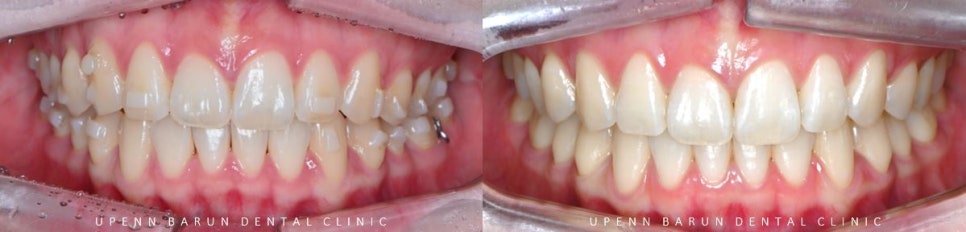

치료 전 사진

교정 전 구내사진

먼저 인비절라인을 시작하기에 앞서

구내 사진을 찍어보았습니다.

정면에서 보았을때

앞니 두개의 모양과 길이만 달라보였으나,

측면 사진을 보니 앞니가 튀어나와 뻐드러져 있고

교합면에서 바라봤을때는 치아끼리 이은 선이

삐뚤빼뚤한 양상을 보였습니다.

교정 전 후를 비교해보니

교정 전

윗니가 아랫니를 과도하게 덮고 있어

답답해 보였던 치아들이

교정 완료 후

과개교합이 개선되고

아랫니들이 더 잘 보이면서 시원해 보이는 느낌을 줍니다.

또한,

정중선이 일치하면서

치아들이 올바르게 배열된 모습을

확인해 보실 수 있습니다.